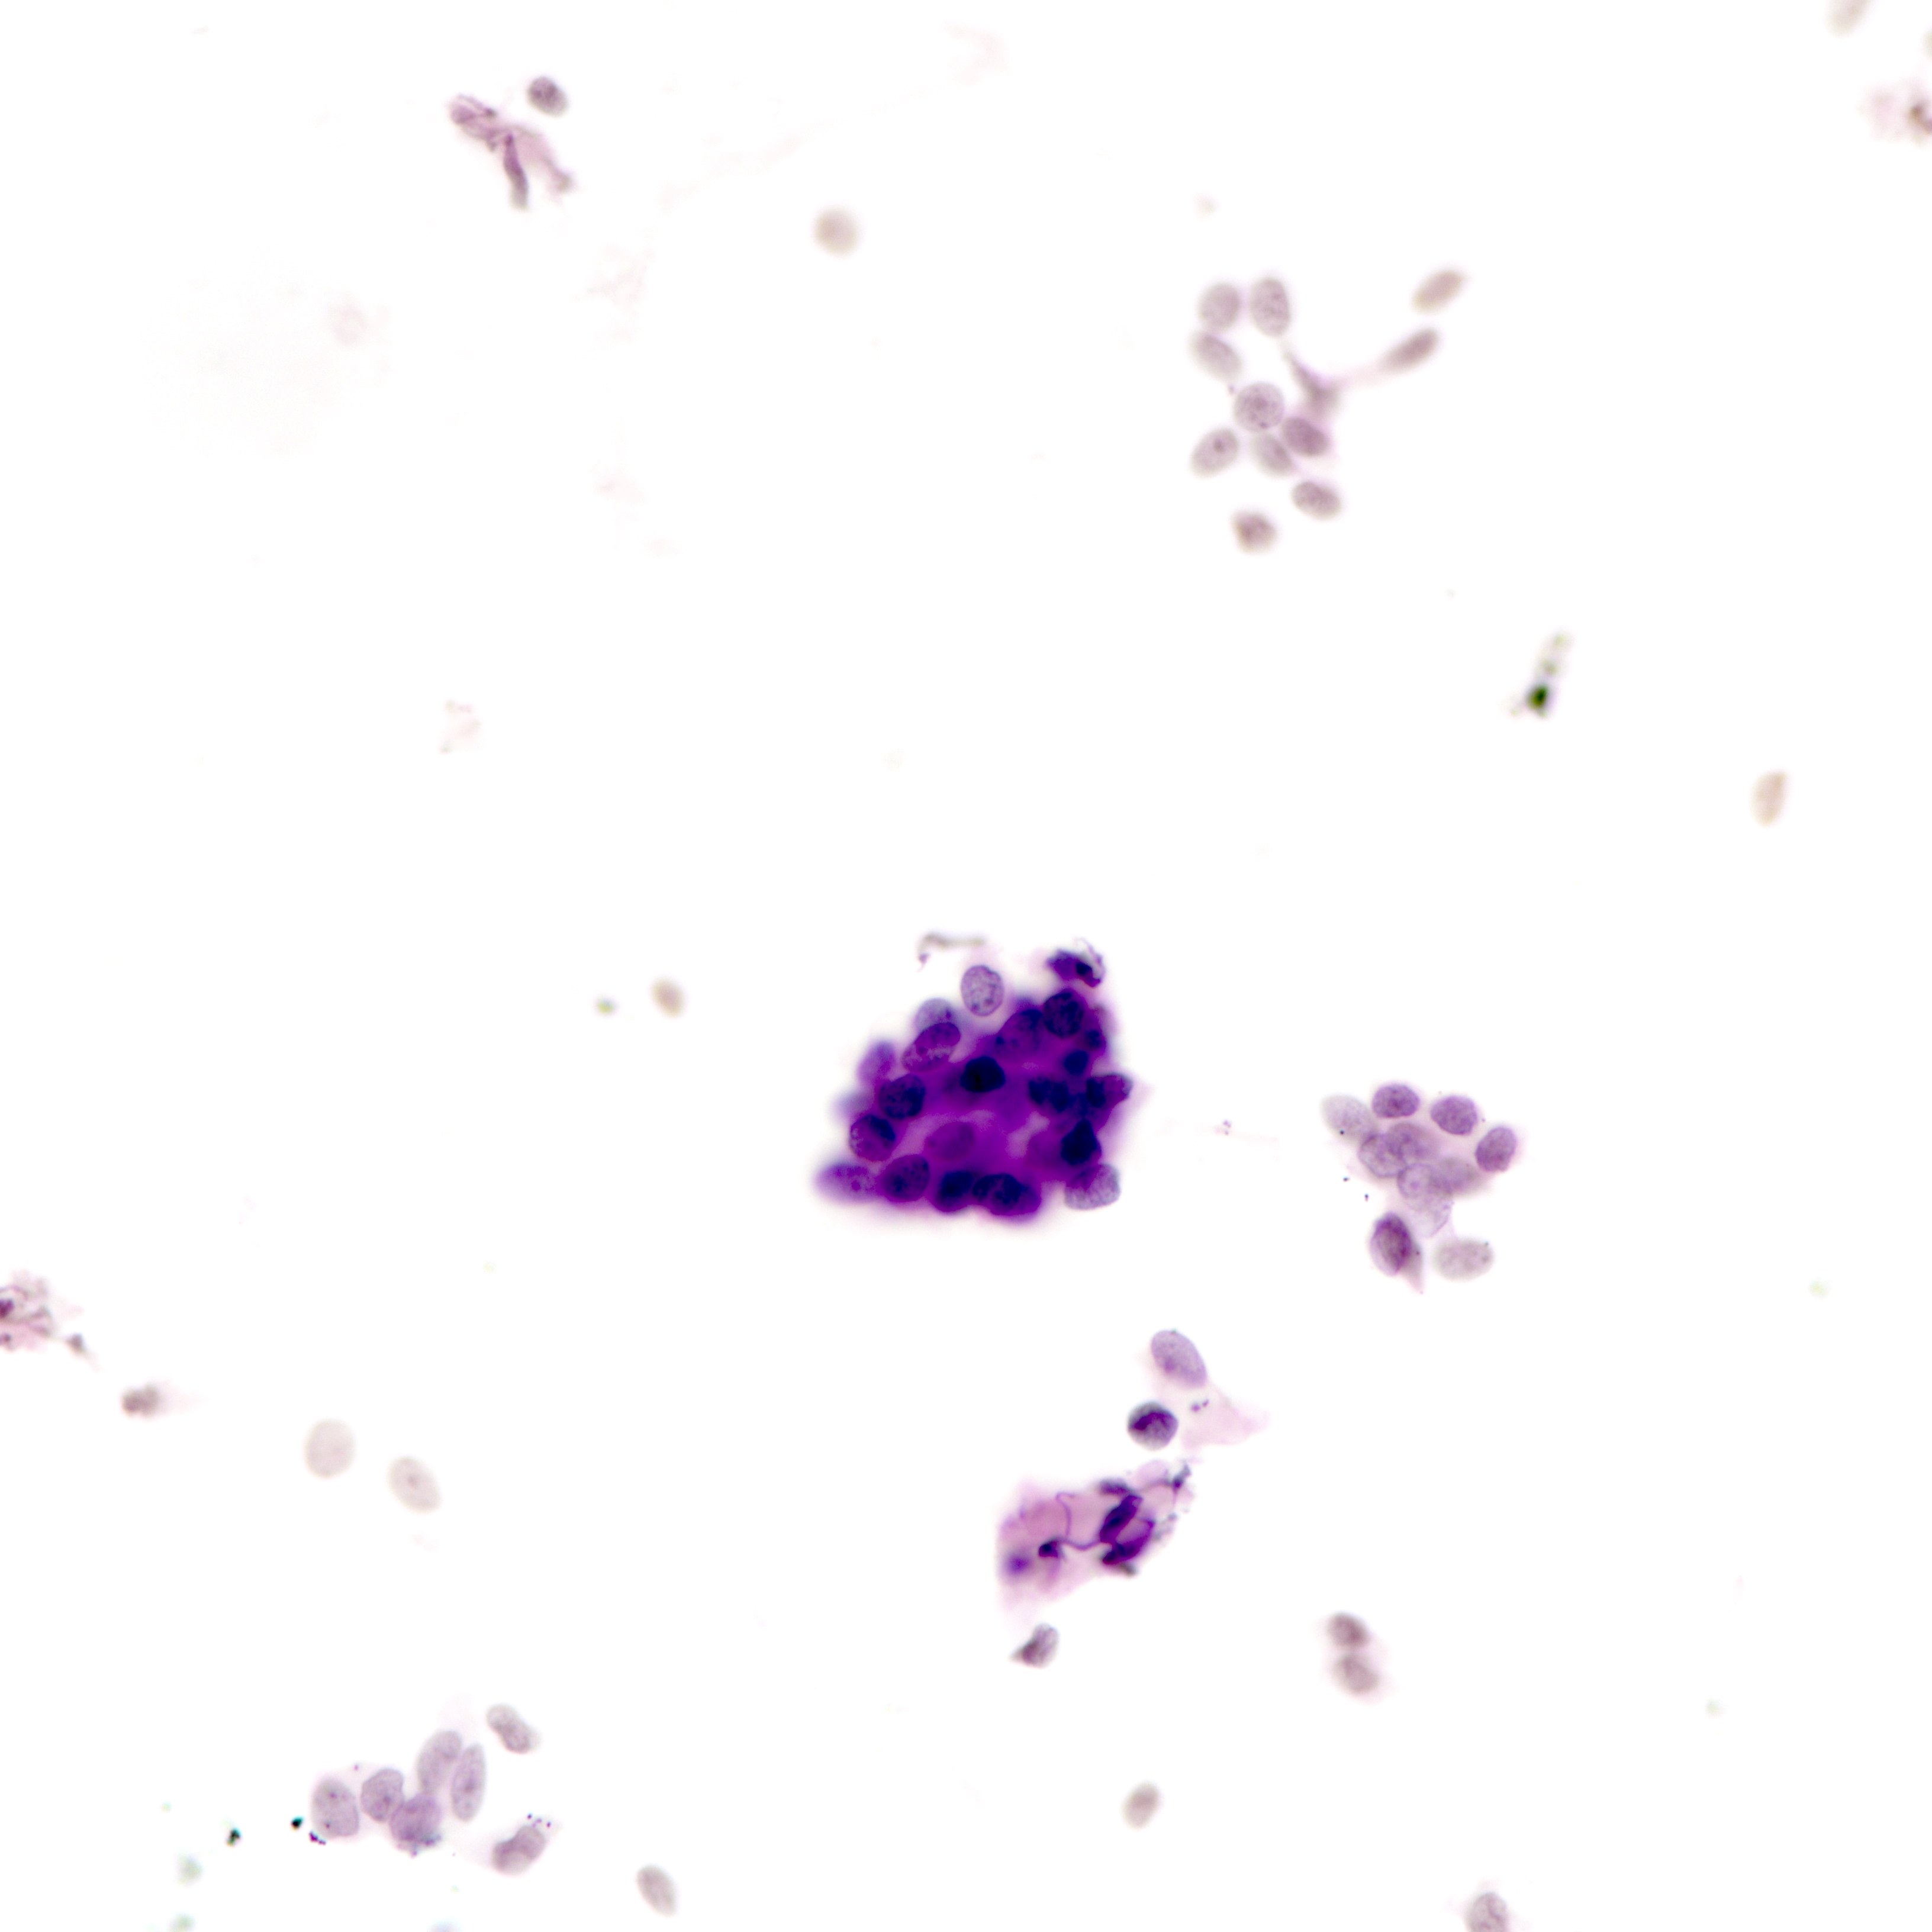

Cytology description

- Tubular fragments (tissue fragments containing multiple tubular structures with or without stroma) is a pathognomonic feature of tubular adenoma (Acta Cytol 2022 Dec 14 [Epub ahead of print])

- Naked nuclei (myoepithelial cells) in the background (N Am J Med Sci 2014;6:219)

- Fibrous fragments scanty (N Am J Med Sci 2014;6:219)

- Epithelial cells arranged in 3 dimensional ball-like structures and probable acinar formations (Acta Cytol 1998;42:657)

- Epithelial cells mostly show bland nuclear features

- Diagnosis based on cytologic assessment only not recommended (N Am J Med Sci 2014;6:219)

Cytology images